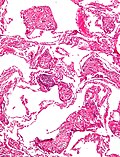

Features:[2]

• Dilated capillaries.

• Blood in airspace, focal.

• Plasma proteins in airspace - light pink acellular junk.

• +/-Hemosiderin-laden macrophages (known as heart failure cells in this context).